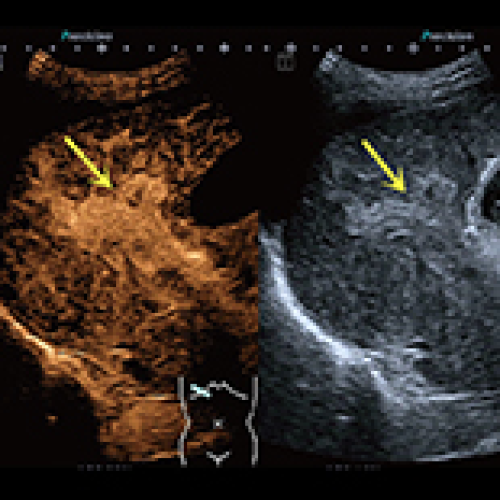

Therapeutic Evaluation of Radiotherapy with Contrast-Enhanced Ultrasound in Non-Resectable Hepatocellular Carcinoma Patients with Portal Vein Tumor Thrombosis

Hongxue Li, Junjie Liu

DOI: 10.12659/MSM.911073

Med Sci Monit 2018; 24: CLR8183-8189